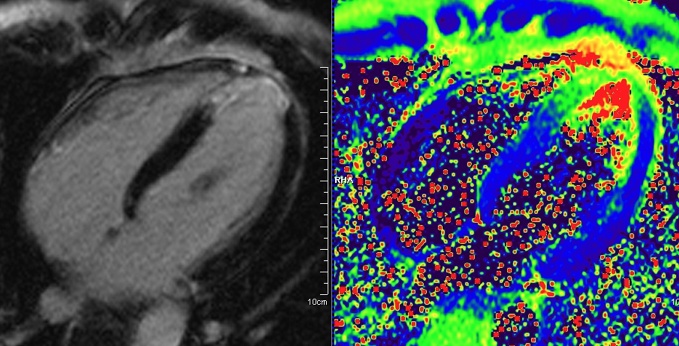

- Technische Innovationen: Ödembildgebung, Mapping, Koronararterien

- Strainanalyse